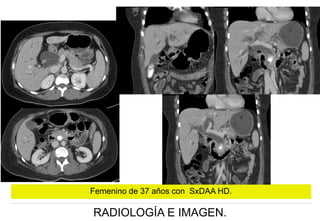

Femenino de 37 años con SxDAA HD.

RADIOLOGÍA E IMAGEN.